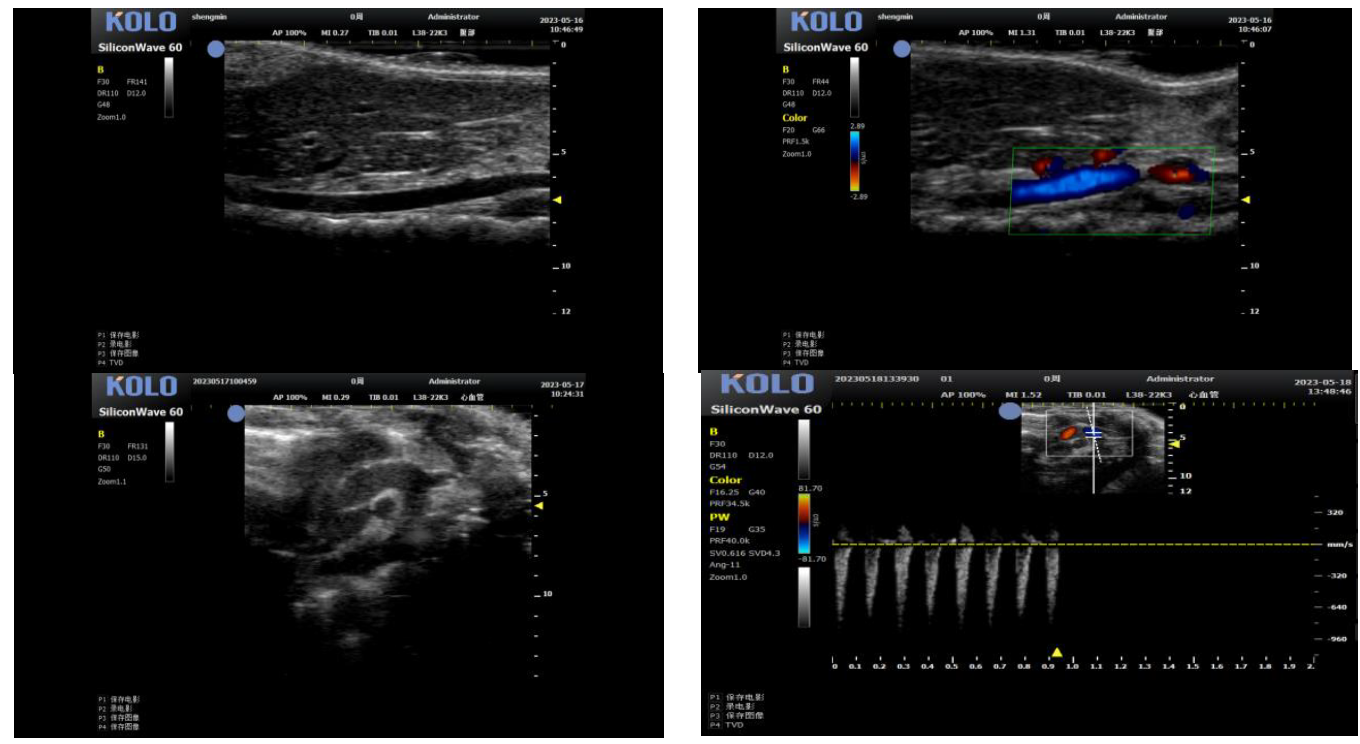

基于CMUT 半导体超声技术,集成多项发明专利,珂纳医疗精心研发出 SiliconWave 60 超高频小动物超声成像系统。该系统微米级的超高清分辨率,8-62 MHz 超宽频段和丰富灵敏的彩色多普勒功能为临床前科研用户观察小动物的心血管、腹部脏 器、浅表组织及胚胎等提供了清晰多彩的超声图像。系统的实时无创操作也为科研实验 的反复验证,长期动态观察等提供了极大的便利性。

3、小鼠血管方面研究

3.1 腹主动脉(长+短轴+管壁距离测量+血流流速)

3.2 颈动脉(长轴)